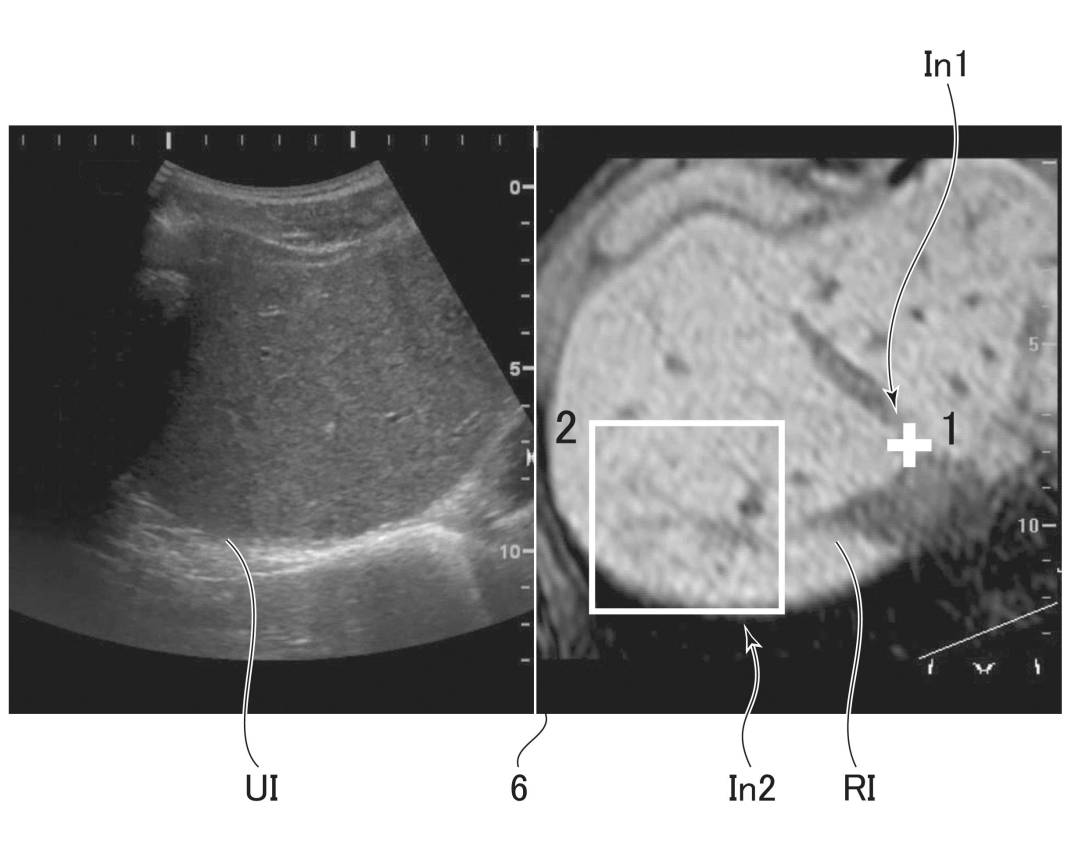

超音波画像表示装置及びその制御プログラム